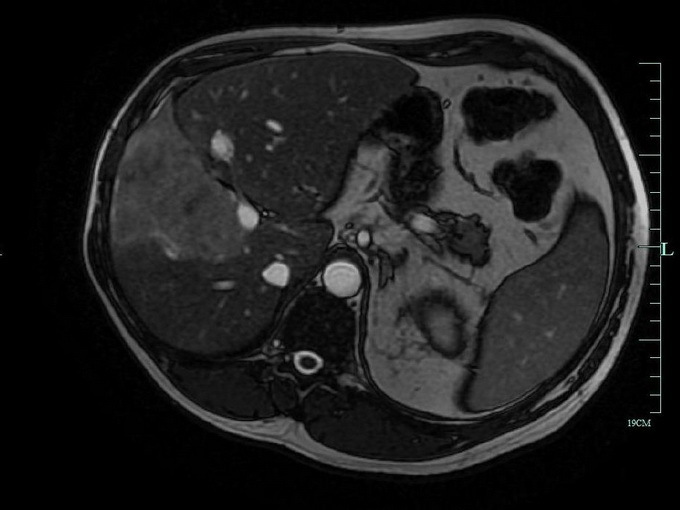

Методы динамического контрастирования печени на МРТ

Раздел: Снимки-подсказки